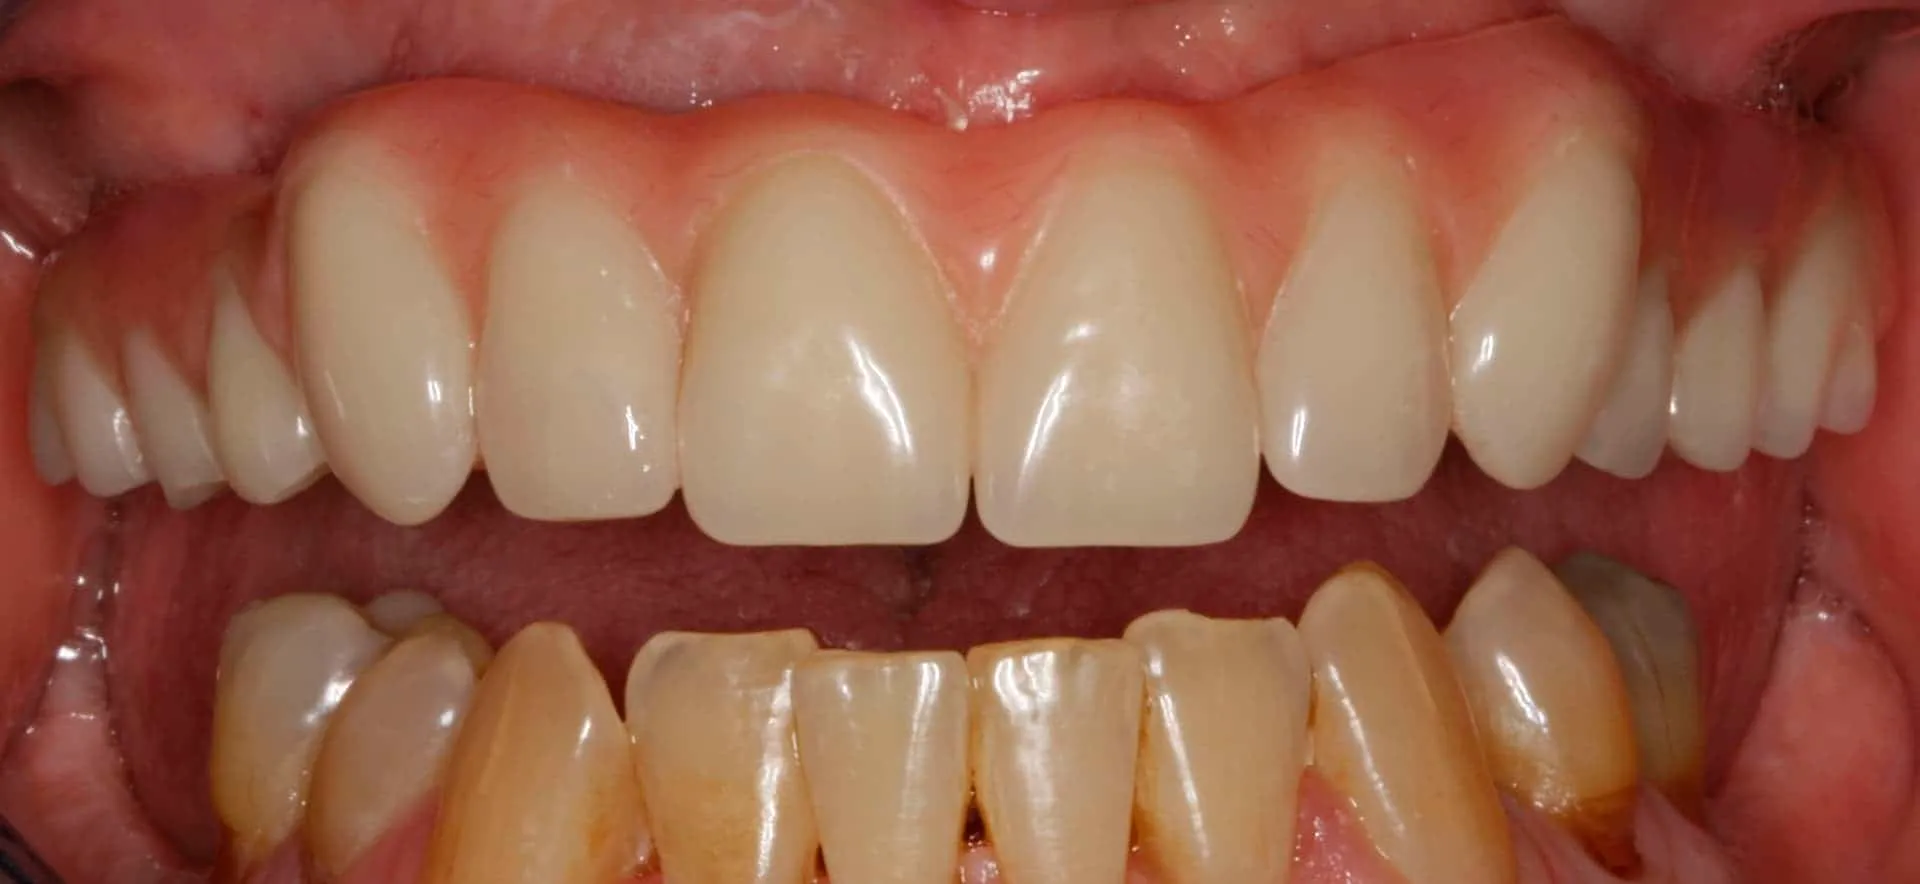

After: Maxillary (upper), acrylic fused to metal, fixed (hybrid) screw-retained (retrievable) restoration supported by 6 titanium root form dental implants. The restoration is fixed, therefore only Dr. Leopardi can remove it for routine maintenance and hygiene, as needed. The patient cleans the fixed restoration as he does his natural lower teeth, with a tooth-brush, floss and water-pick. The outcome is improved function, mastication/diet, aesthetics and quality of life.